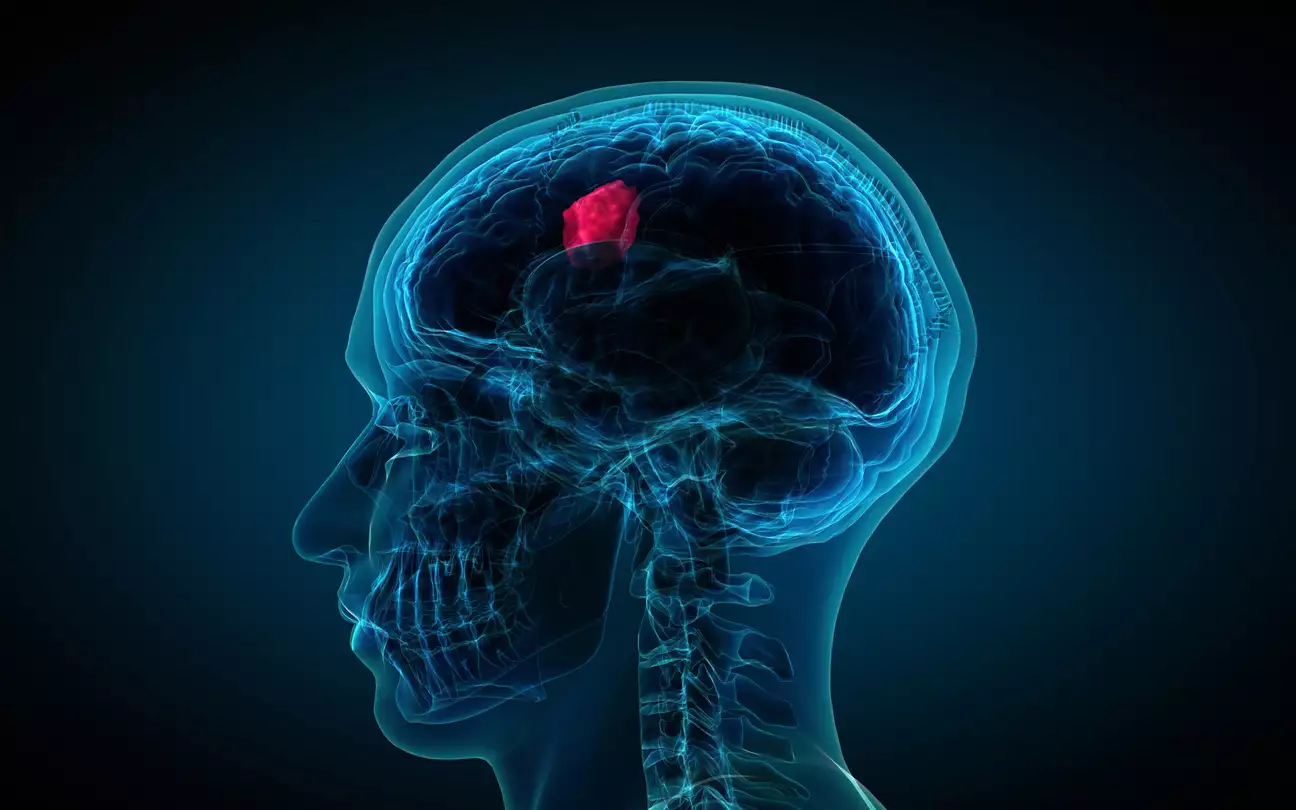

Επειδή ο ανθρώπινος εγκέφαλος είναι τόσο περίπλοκος και εμπλέκεται με εκτεταμένες λειτουργίες του σώματος -όπως η όραση, οι σκέψεις, οι κινητικές δεξιότητες και πολλά άλλα- είναι λογικό ότι τα προβλήματα με την λειτουργία του εγκεφάλου μπορούν να εκδηλωθούν με πολύ διαφορετικούς τρόπους και διακριτικά συμπτώματα.

Η απώλεια της ικανότητας ακρόασης με πολύ συγκεκριμένο τρόπο, για παράδειγμα, μπορεί να είναι σημάδι όγκου στον εγκέφαλο. Υπάρχει ένα σύμπτωμα, ωστόσο, που πολλοί μπορεί να μην δώσουν σημασία και το οποίο οι γιατροί λένε ότι μπορεί να είναι ανησυχητικό.

Πρώτα απ’ όλα: Δεν είναι όλοι οι όγκοι του εγκεφάλου καρκινικοί

Ο όρος «όγκος εγκεφάλου» δεν αναφέρεται μόνο σε ένα είδος όγκου. Υπάρχουν περισσότεροι από 120 διαφορετικοί τύποι όγκων που μπορούν να αναπτυχθούν στον εγκέφαλο, ανάλογα με τον ιστό από τον οποίο προέρχονται. Περίπου 30 στους 100.000 ενήλικες στις ΗΠΑ αναπτύσσουν όγκους του εγκεφάλου κάποια στιγμή στη ζωή τους.

Αν και μερικοί εξισώνουν τους όγκους του εγκεφάλου με τον καρκίνο, μόνο περίπου το ένα τρίτο των όγκων του εγκεφάλου είναι καρκινικοί. Αλλά είτε είναι καρκινικοί είτε όχι, οι όγκοι μπορούν να επηρεάσουν την λειτουργία του εγκεφάλου και την υγεία σας, εάν γίνουν αρκετά μεγάλοι ώστε να πιέζουν τα γύρω νεύρα, τα αιμοφόρα αγγεία και τους ιστούς.